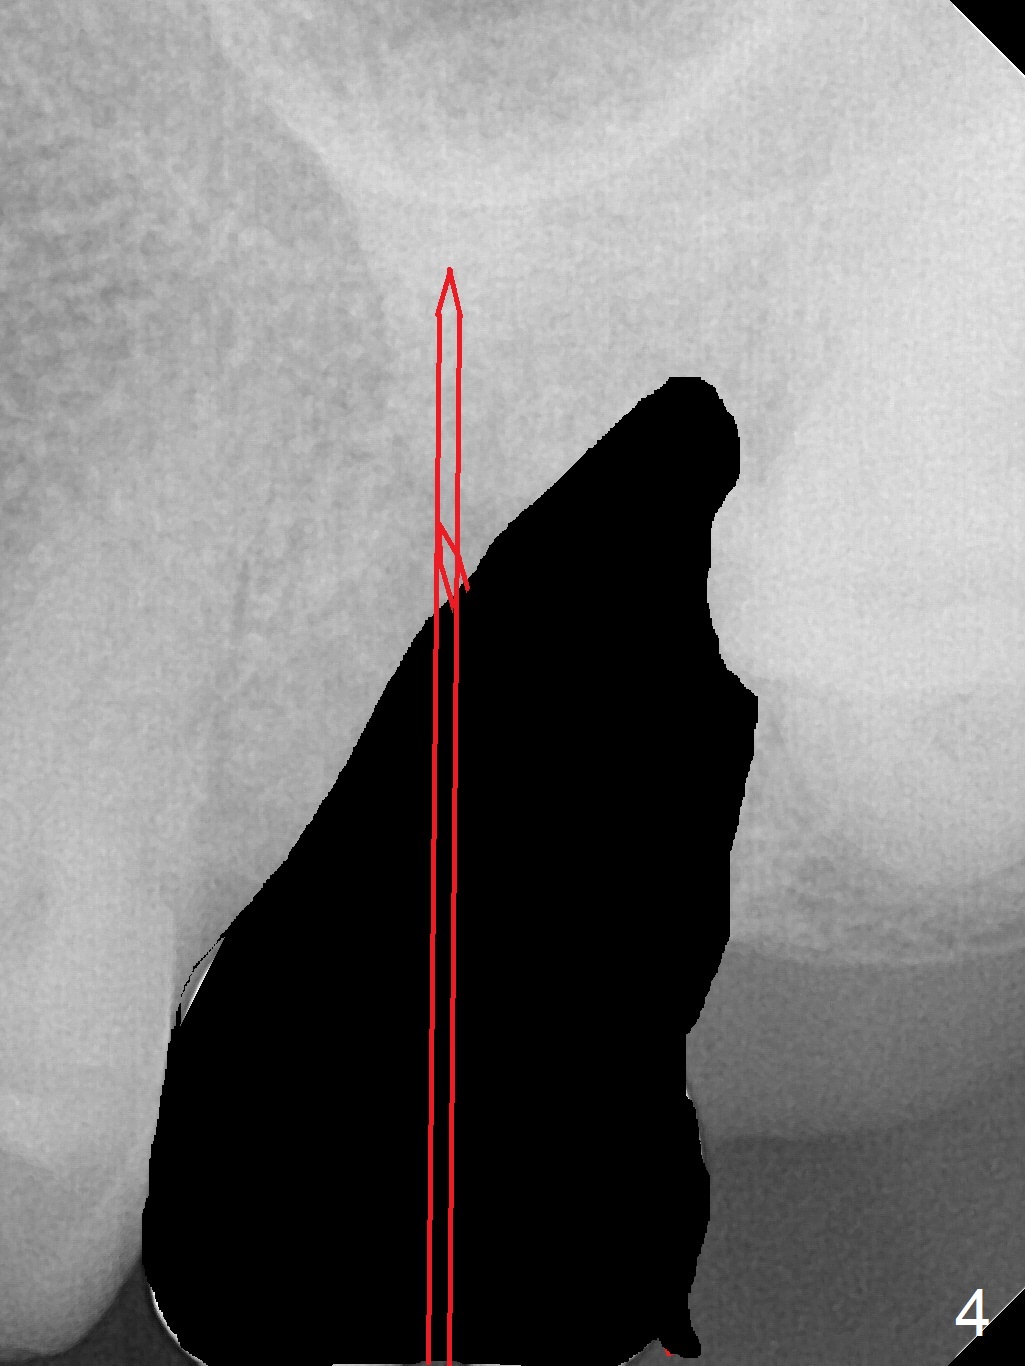

Osteotomy in Mesial Slope A 64-year-old woman will return for extraction/implant for the upper left 2nd molar with a fistula (Fig.1). Since the roots deviate distal (Fig.2 after extraction), initiate osteotomy in the apical 1/3 of the mesial slope with 1.5 mm drill (Fig.3). Once the lamina dura is penetrated, change trajectory (Fig.4) and extend depth for 15 mm (gingival level). After use of 2 mm drill, insert marked parallel pin for PA. The final implant as well as abutment is shown in Fig.5. Return to